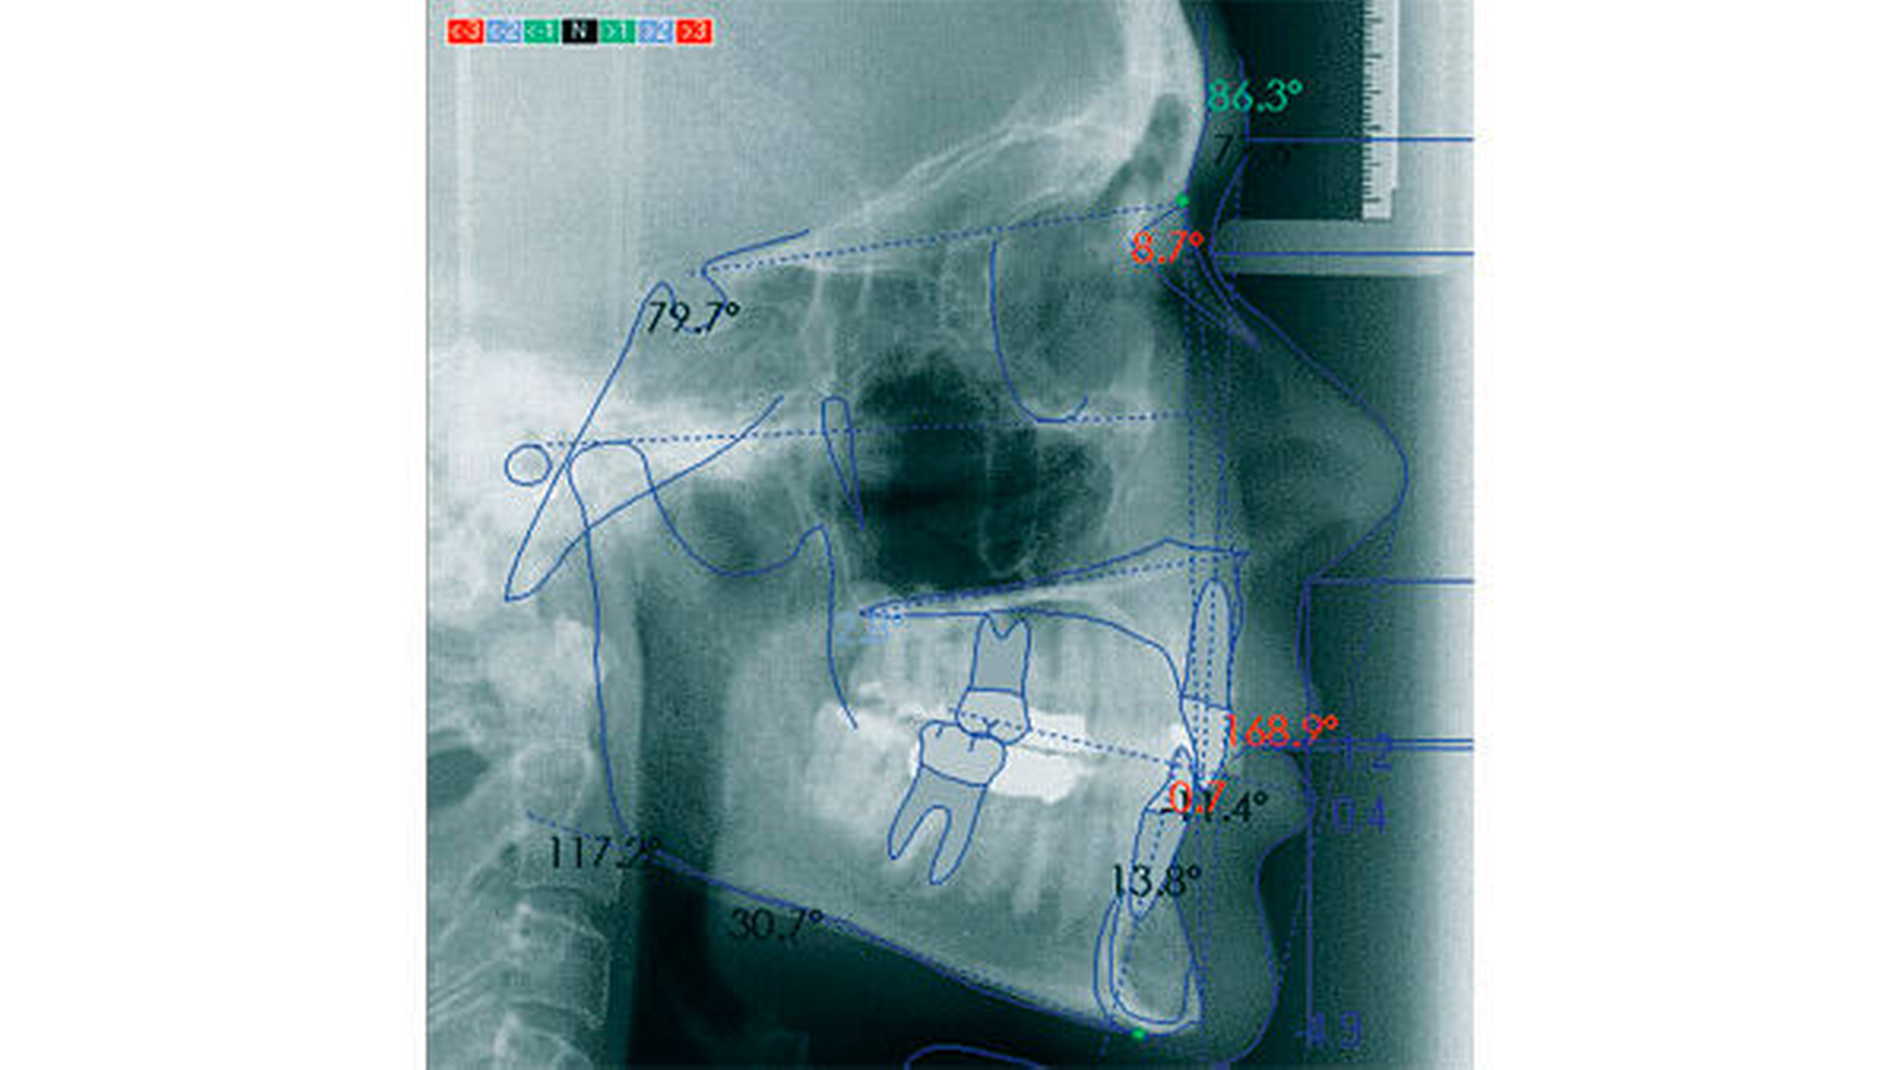

Weil die Zähne heute langfristig im Mund stehen, kommt dem Zusammenspiel zwischen der Zahnstellung und der Kiefergelenksfunktion mit allen anhängenden Strukturen eine viel größere Bedeutung zu als noch zur Zeit meiner Großeltern: Dentale Ursachen eines retralen Zwangsbisses mit den Folgen einer Craniomandibulären Dysfunktion wurden damals durch den Verlust der Zähne gleich mit beseitigt und die Totalprothese konnte an die Kiefergelenksfunktion angepasst werden. Heute müssen und können Zähne kieferorthopädisch so aufgestellt werden [Freesmeyer, 1993; Ernst und Freesmeyer, 2008; Radlanski, 2009], dass sie die Funktion der Kiefergelenke nicht mehr stören (Abbildungen 8a bis 8e). Aber auch hier ist weiterer Forschungsbedarf nötig, denn nicht jede steil stehende Frontzahngruppe führt zwangsläufig zu Fehlfunktionen und Schäden im Kiefergelenk [Freesmeyer, 1993; Köneke, 2010]. Immerhin haben wir jetzt die Möglichkeit, retrudiert stehende Frontzähne länger zu beobachten, da sie nicht mehr regelmäßig einer frühzeitigen vollprothetischen Versorgung geopfert werden.